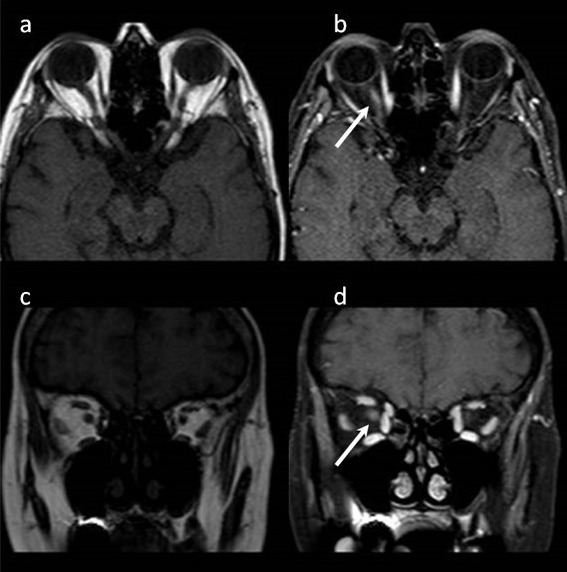

Case description: A 58-year-old woman presented to our clinic with a two-day history of blurred vision in her right eye. She had numerous uveitis attacks previously, and she was on infliximab treatment for ankylosing spondylitis. Her best-corrected visual acuity was counting fingers and 20/25 in the right and left eye, respectively. Optic discs seemed healthy in fundoscopic examination. The right optic nerve showed high signal intensity on magnetic resonance imaging (MRI). Infliximab treatment was discontinued and systemic steroid therapy was started. After the treatment her best-corrected visual acuity improved to 20/20 in her right eye.